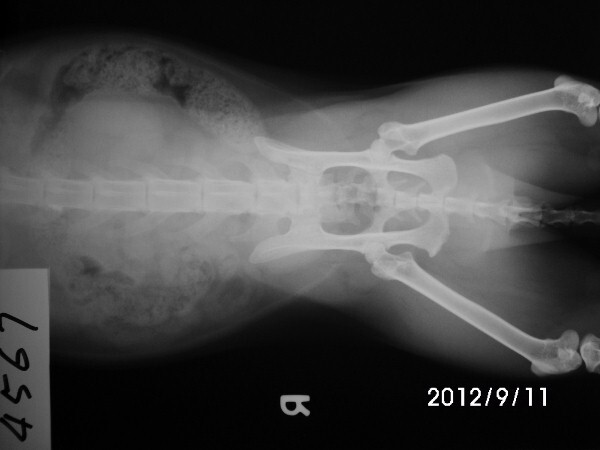

主題: 桂田街 眼睛感染 泌尿道有問題的橘公貓 申請者姓名: 劉雅雲 花色: 申請日期: 2012-09-18 22:30:52 申請者部落格: 申請者臉書網址: 所在縣市/合作醫院: 高雄市/樂生動物醫院 治療費用: 5700元 需求人數: 13人 已結案 (2013-06-27 13:38:03) 報名人員: 阮驛琇(已付款)、姚怡君(已付款)、瑄瑄(已付款)、Leah(已付款)、Pei Jing Gao(已付款)、李孟儒(已付款)、王踢娜(已付款)、Rong Chen(已付款)、Rong Chen、Ginny Cat(已付款)、dowdot(已付款)、KiKi(已付款)、Wen Lin(已付款)、Wen Lin(已付款)、 候補人員: 動物病情說明: 桂田街已經結過紮的橘白公貓, 三年前結紮後跟他的夥伴們在這邊定點餵養, 日前發現眼睛感染越來越嚴重, 又一直有蹲著尿尿的動作, 好像尿不太出來, 很常看到他在蹲, 懷疑有尿道結石或感染的問題. 醫生幫他驗血看有無感染現象, 還有X光照看看有沒有結石, 住院打點滴促進排尿並觀察. 檢查時發現有口腔問題並幫他拔牙與洗牙, 還好沒有尿道結石的問題, 目前治療後眼睛和排尿的狀況已改善, 目前放回原地, 持續餵藥一週和滴眼藥水.

明細如下:

9/11 - 9/17 注院治療 7天 x 300 = 2100

血檢費用 1500

X光照 400 * 2 =800

麻醉洗牙及拔犬齒費用共 1150

眼藥水 150

Total: 5700